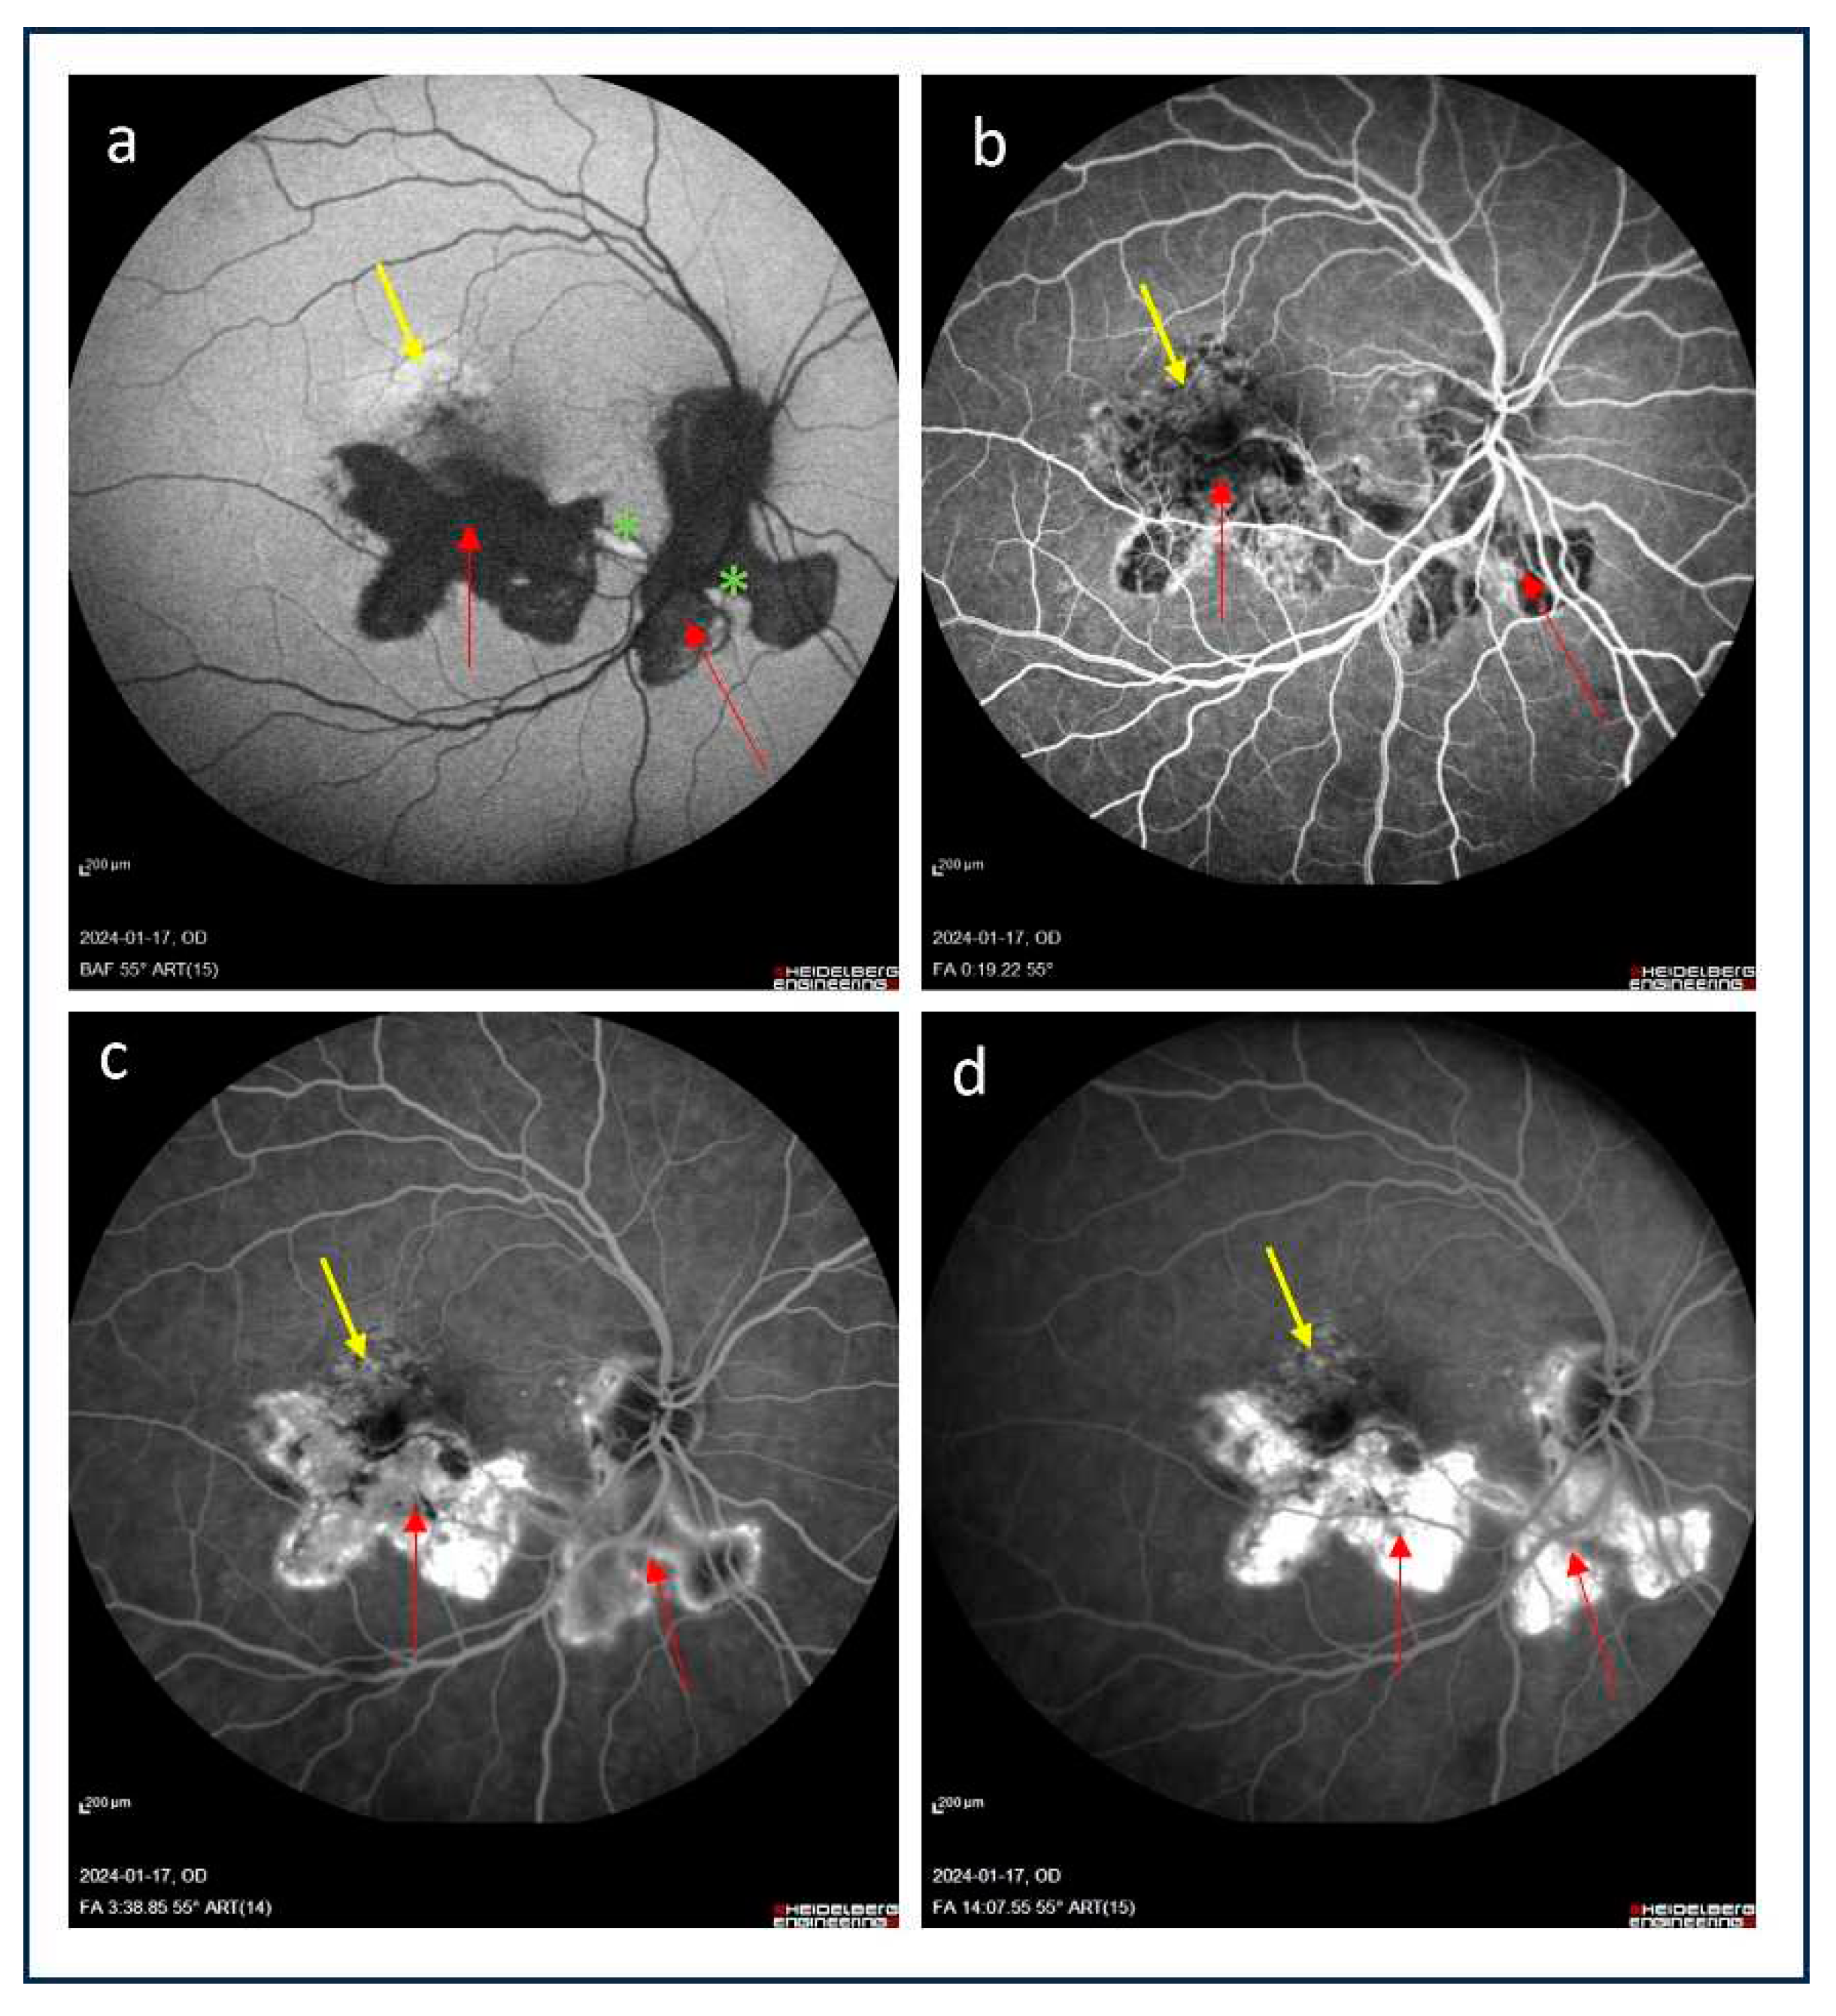

2. Imaging tools for the detection of iCNV

2.1. Fluorescein angiography